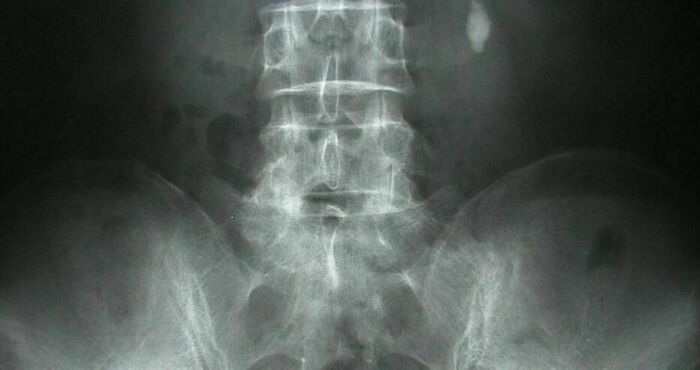

22 декември 1895 г. – Вилхем Рьонтген прави първата рентгенова снимка

При това на своята съпруга. По това време Рьонтген използва уреди, разработени от неговите колеги, за да изследва електрически разряди във вакумирани стъклени тръби. В началото на ноември той провежда опити с катодни лъчи в тръби на Ленард. Тръбата на Ленард е обвита в черна хартия, непропускаща видимата светлина, предизвиквана от катодните лъчи и излъчвана от областта около анода.

На 8 ноември с.г. Рьонтген открива и документира електромагнитното излъчване. Нарича лъчението Х-лъчи, тъй като тяхната природа е била непозната.За това откритие той получава първата Нобелова награда за физика през 1901 г.

Рьонтген забелязва, че намиращите се на известно разстояние от тръбата бариеви кристали светят в тъмнината. При изключено напрежение на тръбата кристалите не светели повече.

Той поставя недалеч от тръбата екран, покрит с бариеви соли, които светвали всеки път, когато включвал напрежението и угасвали след изключването му. Ученият започва да експериментира с различни материали между тръбата и екрана. Картонът, хартията и ебонитът не влияели на яркостта на светене, докато металните предмети хвърляли сянка върху екрана. Той поставя дланта си на пътя на Х-лъчите и на екрана се появява изображение на костите. Меките тъкани обаче се оказват прозрачни за тях.